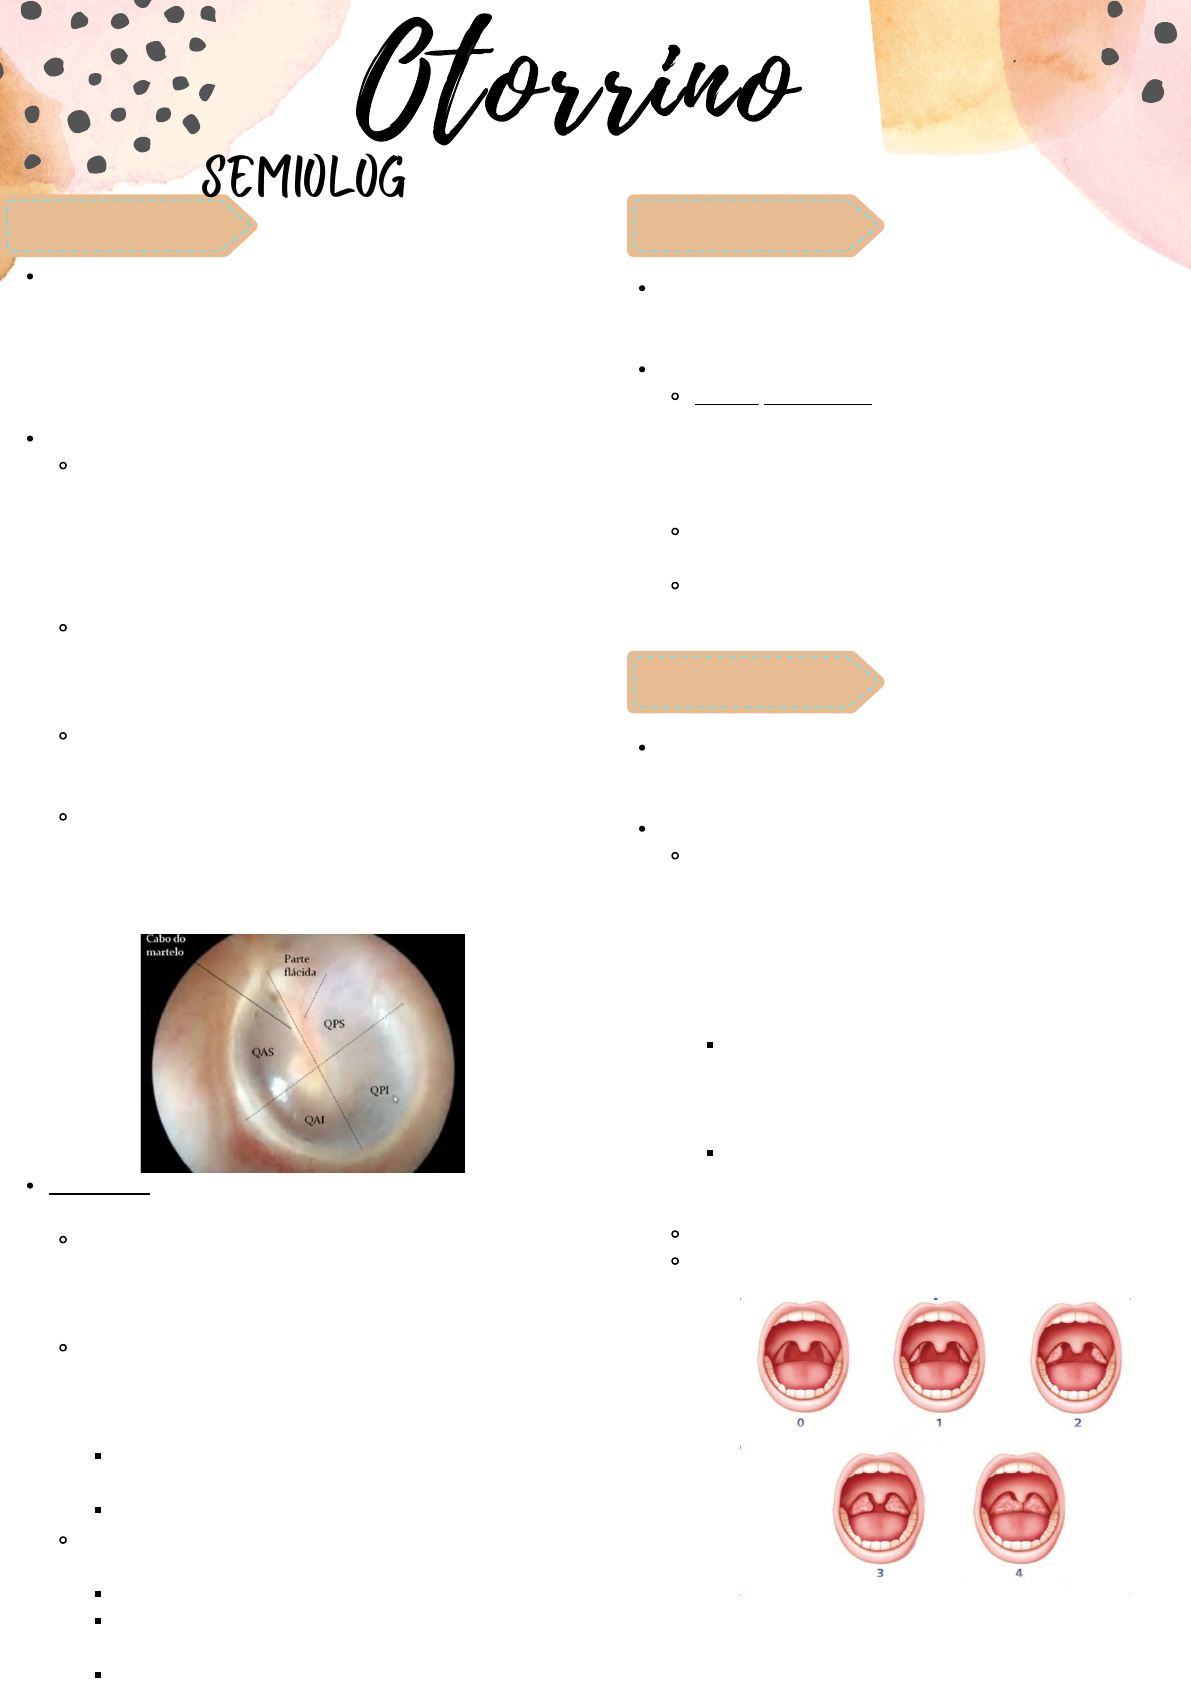

Deve ser visualizado a membrana timpânica e a orelha média.

A partir do cabo do martelo (região mais clara), será dividido

em quatro porções (QAS, QPS, QAI, QPI).

Devem ser analisados cinco aspectos - INTEGRIDADE, COR (o

normal é uma cor de âmbar), TRANSPARÊNCIA

(semitransparente), POSIÇÃO (levemente côncava, com

depressão no umbigo do martelo), MOBILIDADE (analisado

com otoscópio pneumático).